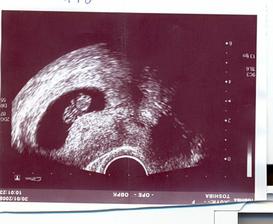

20/2 - 12. týden, kontrola pohmatem, první odběry krve,

19/3 - UTZ, odběry na triple testy,